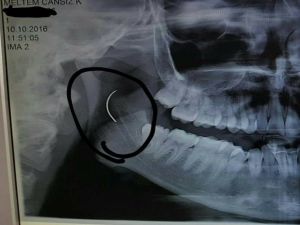

Boğazındaki iğneyle geçen 18 yılını anlatan Meltem Cansız, "3 yaşında geçirdiğim bademcik ameliyatında iğne boğazımda unutulmuş. Daha sonra iğneden dolayı 11 yıl sonra 14 yaşındayken kulak rahatsızlığım ortaya çıktı. Kafamın sağ tarafı ağrımaya başladı. Doktora gittik, hiçbir şey olmadığını söylediler. Sonrasında beni MR çekilmek üzere Akhisar'a yönlendirdi. Gecenin bir vakti MR'a girdim. Ancak bir türlü çekemediler. Benim üzerimde toka vs. metal bir şey olduğunu söylediler baktılar ancak bir şey yoktu. Üç yada dört defa MR'a girdim. Ancak bir türlü çekemediler. Sonra doktorumuz röntgene yönlendirdi. Röntgen görüntüsünde ameliyattan kalma bir çengelli iğnenin boğazımda olduğu görüldü. Bunun için beni Ege Üniversitesi'ne sevk ettiler. Burada doktorlar bu ameliyatı yapabileceklerini ancak riskinin çok olduğunu söylediler. Biz yine de kabul ettik. 1,5 saatlik operasyon geçirdim ancak iğneyi bulmadıklarını söylediler. 2 sene kadar araştırma yaptık. Birçok hastaneyle görüştük. Ancak ayağımda bir rahatsızlık meydana geldi. Ayağım için Ege Üniversitesi'ne gittik. Tekrardan beni ameliyat eden doktorumla görüştüm. "Seni ben ameliyat ettim, tekrardan buna kalkışamam" dedi. MR'a da giremezsin dediler. "Sen bununla yaşamayı öğren" en azından bunun için çabalama alınmaması daha iyi dediler. Ben daha genç bir kızım sonuçla bu iğneyle ömür boyu yaşayamazdım. Yaşanan bu olumsuzların ardından araştırmalarımız neticesinde en son İzmir'de özel bir hastaneye gittik. Oradaki doktorum Çağlar Çallı bey bana umut verdi. "Bu iğneyi alacağız" dedi. İnancımı kaybetmedim, sonucun ne olacağını bilmeden girdim ben o ameliyata. Ölüm, felç olma riskim çok fazlaydı. "Yaşayamayabilirsin" dediler, biz bile bile lades dedik. Sonucu da güzel oldu" dedi.

Baba Ahmet Cansız ise kızını 1999 yılında 3 yaşındayken bademcik sorunu nedeniyle Soma Devlet Hastanesi'ne götürdüğünü belirterek, "Bademcikleri nedeniyle çok sık hasta oluyordu. O günkü SSK'da doktorumuz ameliyat olması gerektiğini söyledi. Neticede ameliyat olduk. Ameliyat sonrasında aradan geçen süreçte kızım 17 yaşında geldiğinde yüzünde, sağ tarafında bir ağrının olduğunu, başının, kulağının ağrıdığını söyleyince kulak burun boğaz doktoruna gittik. İlaçlar verdi geçmedi, sonra bir daha gittik. Eklem arası bir iltihap olabilir diyerek MR istedi. Akhisar ilçesine MR çekilmeye gittik. Fakat bir türlü çekemediler. Daha sonra bir film çekildi ve iğne ortaya çıktı" diye konuştu.

Ege Üniversitesi'ne gittiklerini belirten baba Cansız, iğnenin şah damarına çok yakın olduğunun söylendiğini belirterek şunları söyledi: "Doktorlar çok tehlikeli bir ameliyat olacağını yanlış ya da en ufak bir hatada kızımızın bir tarafının felç kalabileceğini veya hayatını kaybedebileceğini söylediler. Biz bu riski göze alarak ameliyata müsaade ettik. Fakat iğneyi görüldüğü yerde bulamadıklarını söyleyerek alamadılar. Sonra İzmir Çiğli'de özel bir hastanede denedik. Kendisine binlerce kez teşekkür. Allah razı olsun. Çocuğumun boğazındaki iğneyi aldı. Dünyalar bizim oldu."